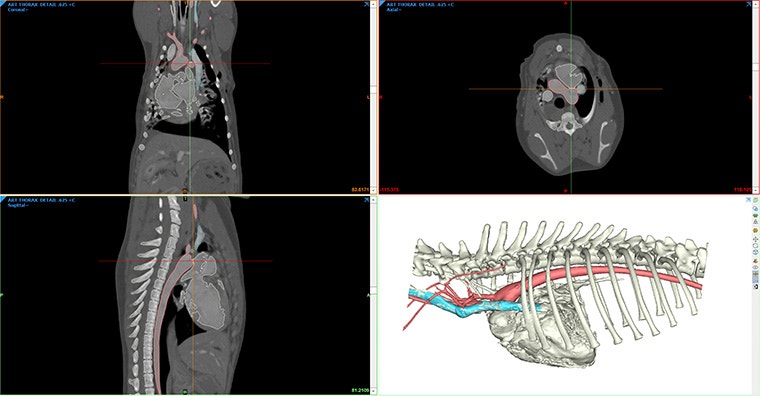

Create detailed, patient-specific 3D models from CT and MRI scans with Mimics. You'll visualize complex anatomical structures with unparalleled accuracy for more precise and effective surgical interventions.

From routine procedures to advanced surgeries like maxillofacial reconstructions, this versatile tool supports a wide range of veterinary applications.